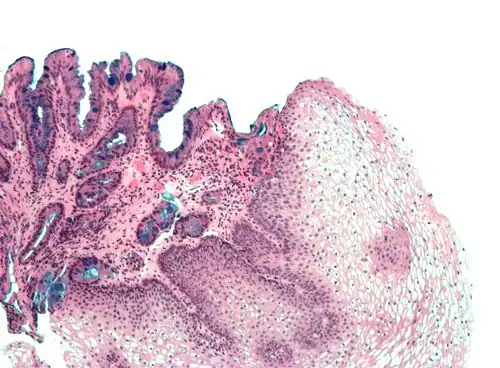

H&E stain of biopsy of normal esophagus showing the stratified squamous cell epithelium.

Section of the human skin showing the stratified squamous epithelial surface, referred to as the epidermis. The layer of keratin here is named the stratum corneum.

A stratified squamous epithelium consists of squamous (flattened) epithelial cells arranged in layers upon a basal membrane. Only one layer is in contact with the basement membrane; the other layers adhere to one another to maintain structural integrity. Although this epithelium is referred to as squamous, many cells within the layers may not be flattened; this is due to the convention of naming epithelia according to the cell type at the surface. In the deeper layers, the cells may be columnar or cuboidal.[1] There are no intercellular spaces. This type of epithelium is well suited to areas in the body subject to constant abrasion, as the thickest layers can be sequentially sloughed off and replaced before the basement membrane is exposed. It forms the outermost layer of the skin and the inner lining of the mouth, esophagus and vagina.[2]